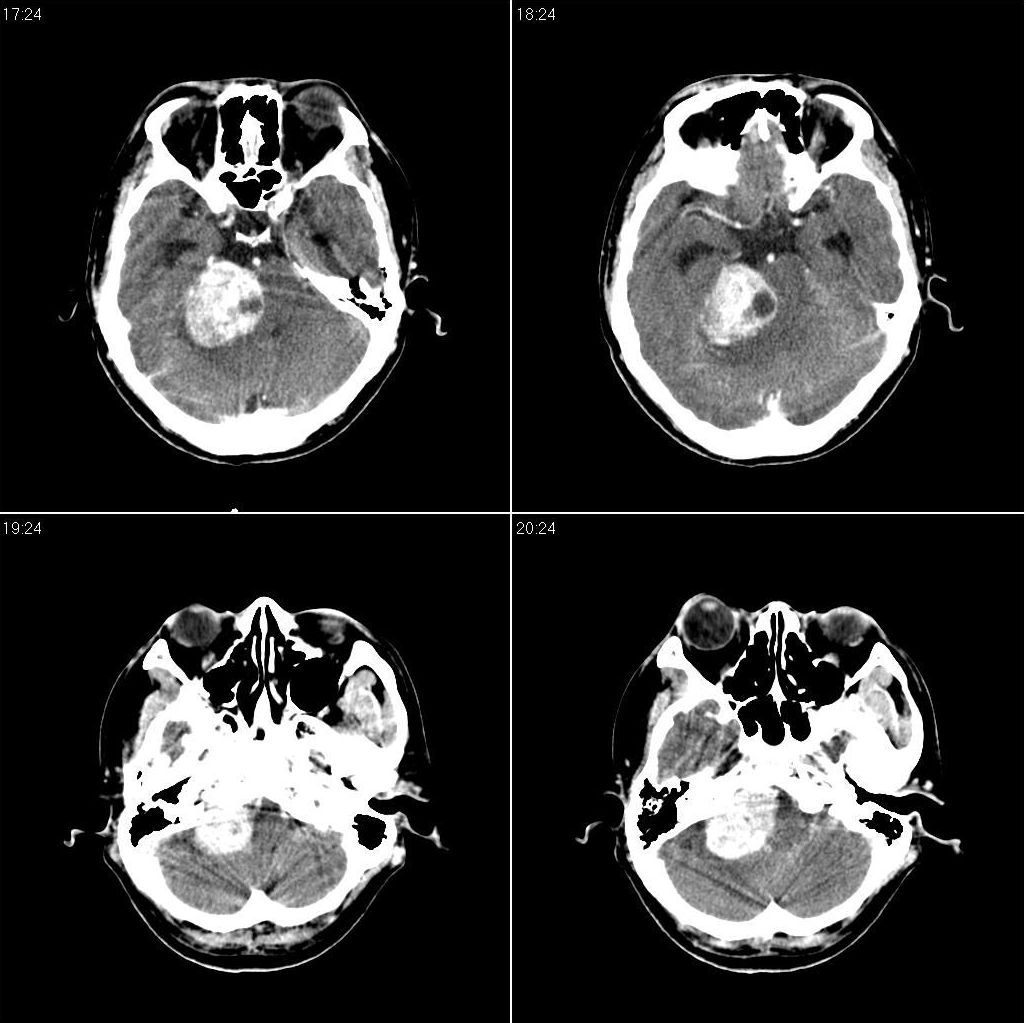

标题: 上传增强片,看看到底是什么肿瘤:

[本贴已被 fanshl 于 2008-11-20 4:13:58 修改过]